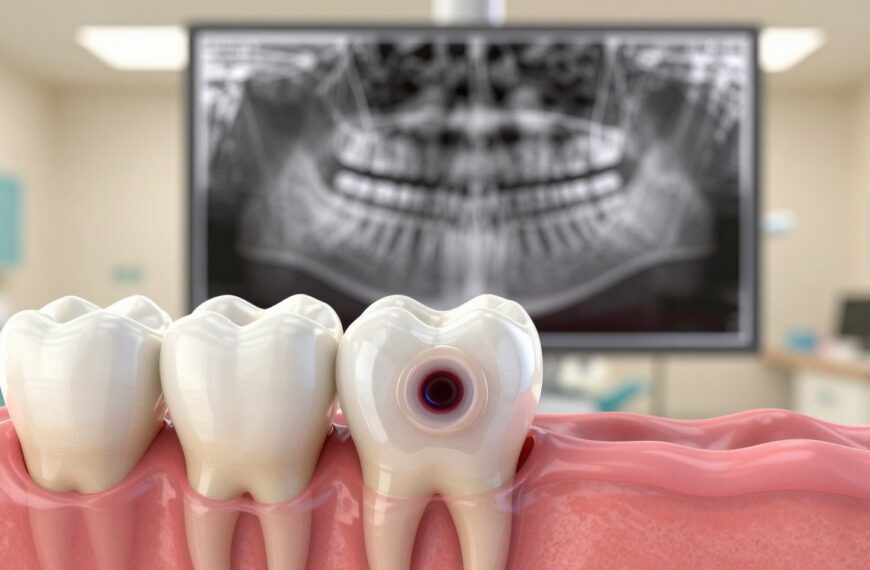

Dowiedz się więcejZapalenie miazgi zęba – ile trwa ból i kiedy leczenie kanałowe jest jedynym wyjściem

Czy nagły, pulsujący dyskomfort może zniknąć sam, czy raczej zwiastuje poważniejszy problem? Ten wpis wyjaśni, dlaczego pytanie o …

Zapalenie miazgi zęba – jak uśmierzyć ból doraźnie i kiedy potrzebne jest leczenie kanałowe

Czy nagły, pulsujący dyskomfort w jamie ustnej może być sygnałem czegoś poważniejszego? To pytanie warto zadać przy pierwszym nasileniu dolegliwości. Stan zapalny we wnętrzu zęba często daje ból samoistny, promieniujący…